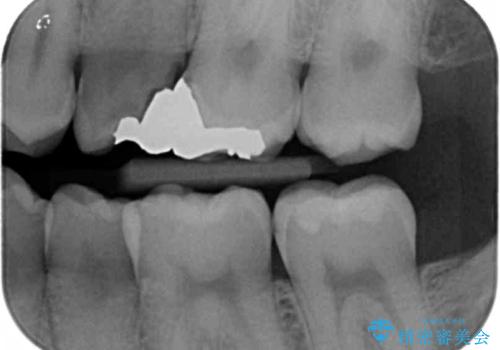

- ねじれてしまっている奥歯の矯正治療、銀歯のセラミック治療を求めて来院されました。

銀歯を外す前に部分矯正治療を行うことで歯のポジションを調整したのち、セラミック治療を行います。

90°ねじれてしまっていた歯を、矯正治療で治し、前後の歯の咬合関係も改善してしっかりと噛めるようになりました。